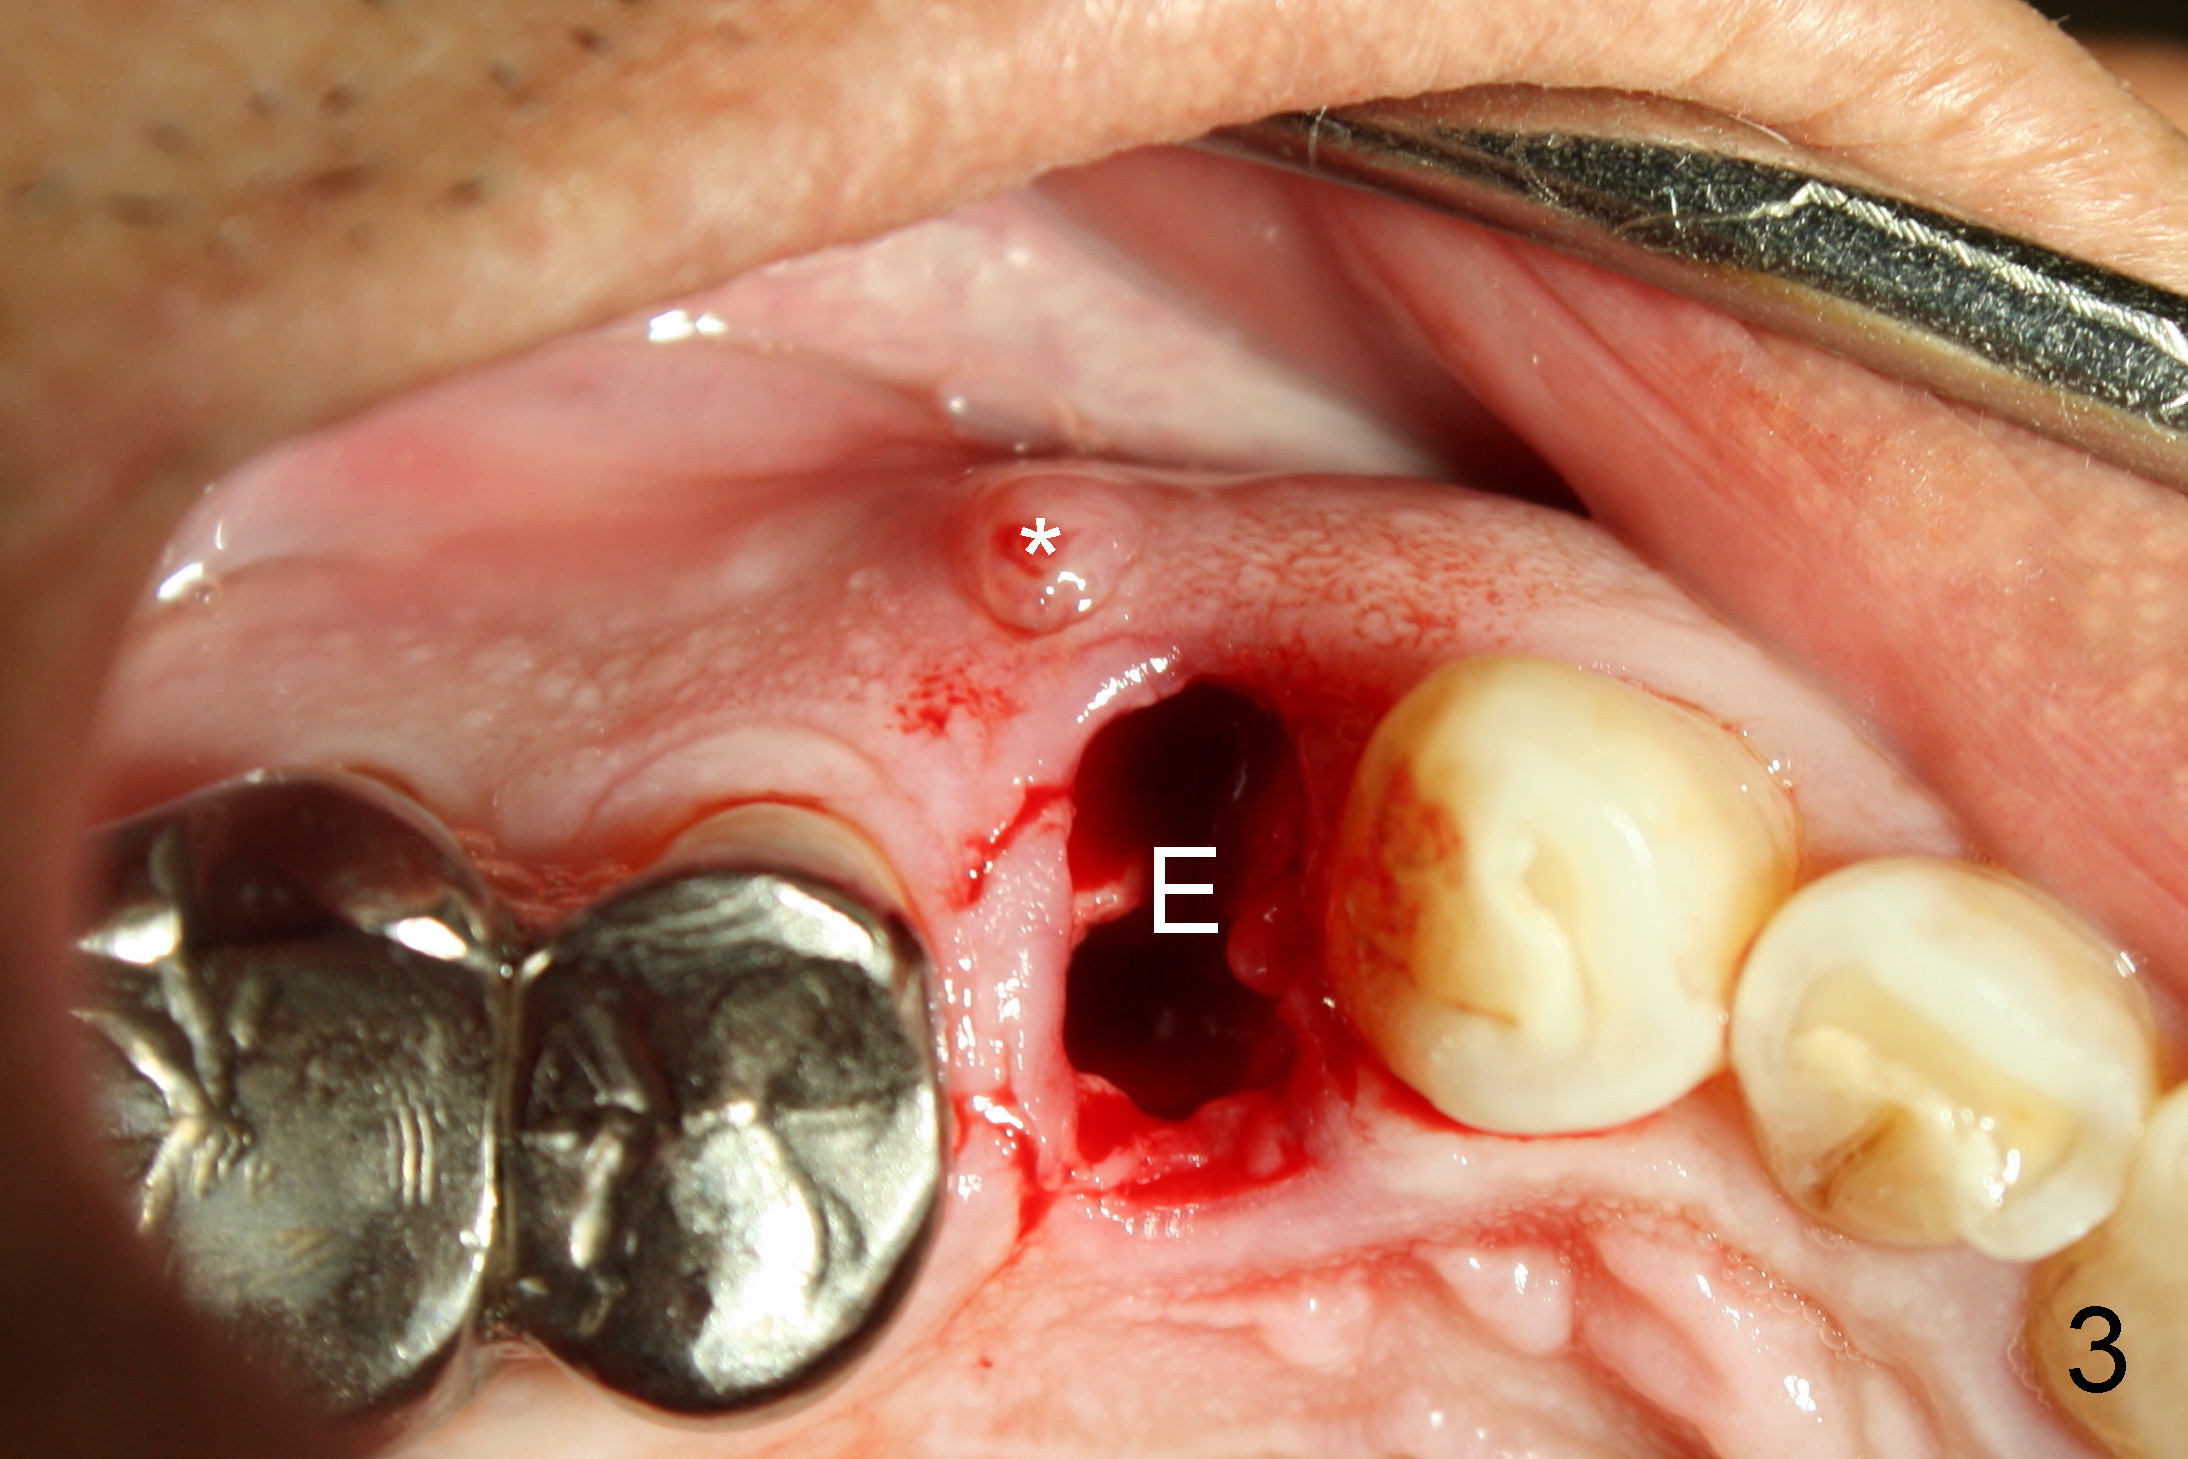

A 68-year-old man has pain and swelling associated with the tooth #5 (Fig.1). The fistula (*) is connected to the periapical radiolucency using a gutta percha (Fig.2 <). There are deep pockets distobuccal and lingual. The lingual root is found to have oblique fracture upon extraction. The distobuccal plate perforates (Fig.3). Collagen plug is placed. The buccal plate is concave (Fig.4) and socket density is low 2.5 months post extraction. Three months post extraction a 4.5x8 mm Bicon implant is placed after reamer and osteotome osteotomy (Fig.6). Bone density around the implant appears to increase 5 months post placement (Fig.7). Porcelain-fused-to-metal crown is cemented 2 weeks later. Bucco-occlusal porcelain chips 2 months post cementation. The patient decides to redo the crown. PA is taken before crown removal (Fig.8: 3 year 10 months post cementation). When a straight abutment is removed (Fig.9 A), a 15° angled abutment has to be used (Fig.10 red) for restoration.